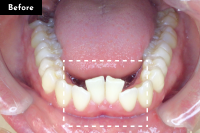

Basicプラン

上下前歯12本の部分矯正

20代 女性

治療費用:Basic 33万円(税込)

治療期間:4ヶ月

- Before

After